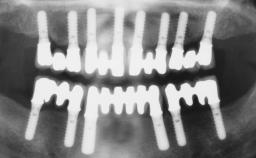

Immediate Loading of Six Implants in the Mandible and Six Implants in the Maxilla and Final Restoration with Full-Arch CAD/CAM Metal Framework FDPs Involving Digital Planning and Guided Surgery

Immediate loading of dental implants is increasingly popular with clinicians and patients. The idea of delivering a restoration directly after implant insertion,combined with a less invasive procedure (flapless protocol), has made treatment protocols involving dental implants more accessible to dentists and patients. However,immediate-loading concepts require sophisticated and exact planning. To facilitate this, conventional panoramic tomographs and periapical radiographs are often taken with the patient wearing a radiographic template simulating the preoperative prosthetic design. However, these radiographs do not provide all the necessary information. In addition, some protocols call for conventional surgical templates fabricated on the diagnostic cast. These will inform the bone drilling points and drill angles, but do not reference the underlying anatomical structures or provide exact 3-D guidance.

# of Implants 12

Guided Surgery Yes

Abutment Type CAD/CAM

Prosthesis Type FDP